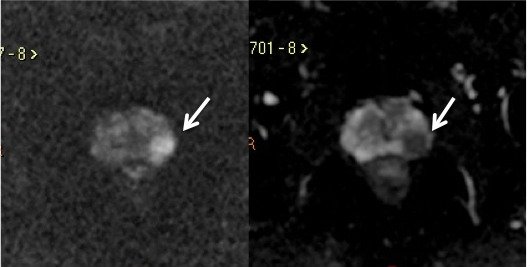

A Difusão (DWI - Diffusion weighted imaging) estuda o movimento randômico das moléculas de água nos tecidos, estimando indiretamente a densidade celular e a viabilidade das membranas celulares. A sequência gera múltiplos conjuntos de imagens, de acordo com o número de fatores de difusão ou “valores de b” escolhidos. O aparelho também gera um mapa de coeficiente de difusão aparente (ADC – apparent diffusion coefficient), que é um conjunto de imagens que permite a quantificação das propriedades de difusão. Desta forma, uma lesão com difusibilidade restrita aparece como uma área hiperintensa no DWI, e com redução da intensidade de sinal no mapa ADC.11

A restrição à difusão das moléculas de água no câncer de próstata é atribuída ao aumento da celularidade das lesões malignas, com redução do espaço extracelular, e consequente restrição à livre movimentação das moléculas de água. Portanto, a DWI tem o potencial de diferenciar lesões benignas de malignas, sendo fundamental na detecção do câncer de próstata.13,19(fig. 7).

Figura 7. Mesmo paciente da figura 4, imagem ponderada em Difusão (A) e o mapa de ADC (B) mostram lesão na zona periférica esquerda, com intensa restrição à difusão das moléculas de água, caracterizado por hipersinal no DWI e baixo sinal no mapa de ADC.

Em uma metanálise recente, a DWI isolada apresentou sensibilidade de 62% e especificidade de 90% no diagnóstico do câncer de próstata. A sensibilidade é maior quanto maior o volume tumoral e o escore de Gleason. É importante ainda ressaltar que a sensibilidade da difusão para a detecção do câncer de próstata é muito maior na zona periférica, em torno de 79%.19A DWI é limitada na avaliação da glândula central, já que nódulos de hiperplasia prostática podem apresentar restrição variável à difusão. Para tumores da glândula central, as imagens ponderadas em T2 parecem ter melhor capacidade de detecção do câncer do que a difusão.14

Estudos têm demonstrado ainda que os valores de ADC têm forte correlação com a agressividade tumoral, sendo que tumores com escore de Gleason maior apresentam valores de ADC mais baixos. Portanto, além do diagnóstico, a Difusão fornece informações relativas ao prognóstico.11

Limitações da DWI incluem baixa resolução espacial e maior risco de degradação das imagens por artefatos de susceptibilidade magnética. Devido à baixa resolução espacial, a difusão é limitada para o estadiamento locorregional, sendo as imagens ponderadas em T2 fundamentais para esta avaliação.11